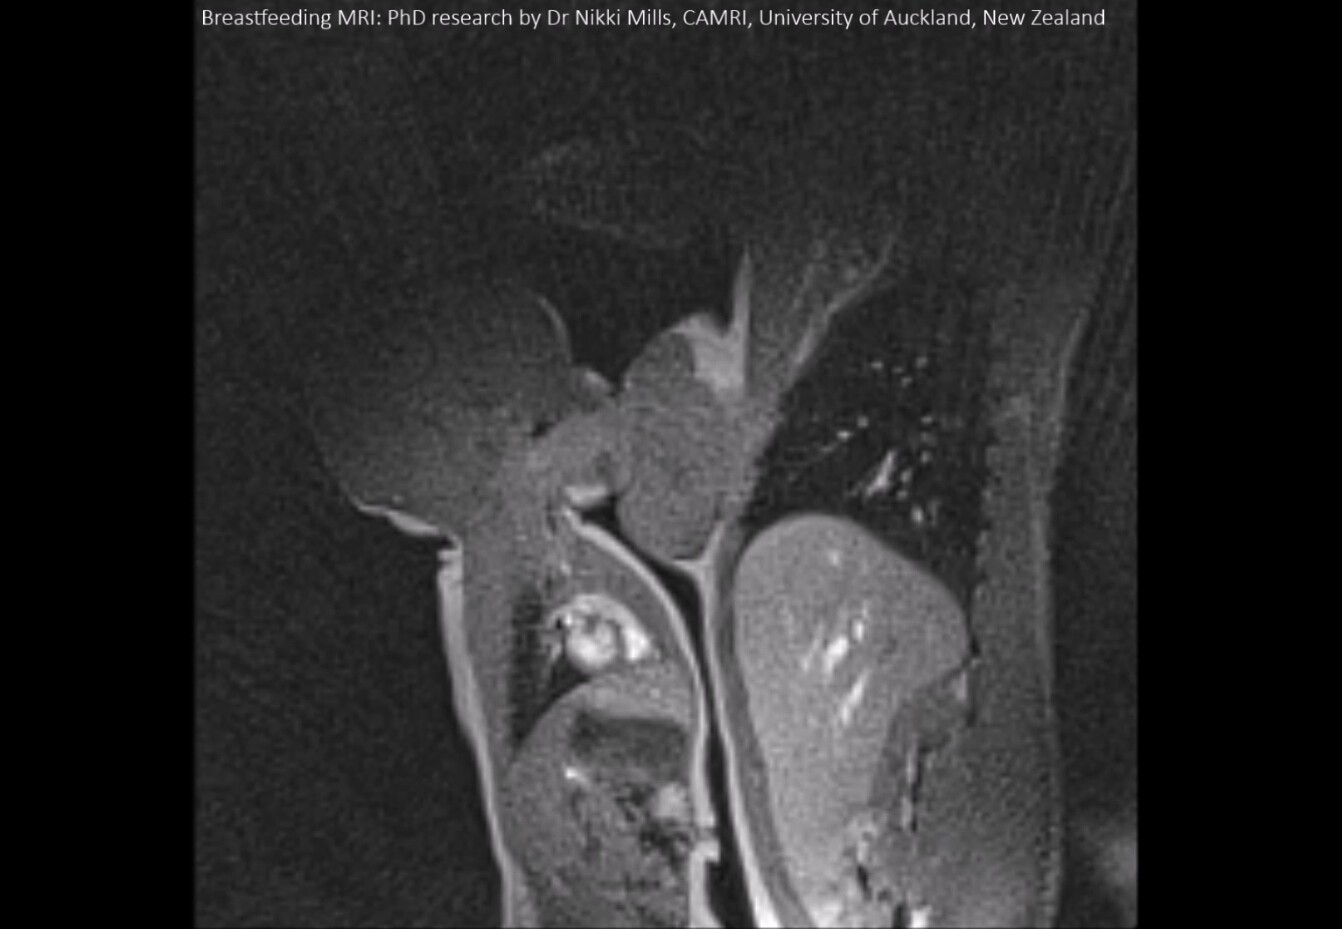

Aunque en teoría ya sabemos "cómo funciona" la lactancia, un estudio realizado en Nueva Zelanda obtuvo por primera vez imágenes claras de la lactancia materna a través de una resonancia magnética, mostrándonos en tiempo real la deglución del bebé.

Como parte de una investigación para analizar cómo es el mecanismo de deglución de los bebés lactantes, investigadores de varias universidades en Nueva Zelanda realizaron una serie de pruebas utilizando resonancias magnéticas en madres e hijos.

Para ello, se contó con la participación de 12 parejas de mamá y bebé, de los cuales se logró capturar con éxito a 11 bebés con imágenes estáticas y nueve bebés con imágenes dinámicas, entre las que se encuentra este vídeo, en el que podemos observar cómo pasa la leche materna de la boca del bebé a su estómago.

Los investigadores señalan que gracias a estas imágenes han podido confirmar que la superficie dorsal de la lengua del bebé eleva el pezón materno hacia el paladar duro, cerrando el espacio alrededor del pezón en la cavidad oral durante la succión y la deglución.

Aunque también comentan que debido al movimiento del bebé y la densidad en los tejidos de labios, lengua y pezón no pudieron definirlos claramente entre ellos, sin duda resulta impresionante ver cómo el bebé sabe exactamente qué hacer para alimentarse y cómo la leche viaja directamente de su boquita hasta su estómago.